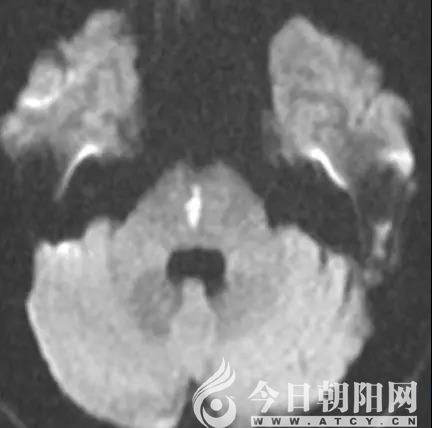

患者術(shù)前磁共振影像

患者術(shù)后磁共振影像

9點(diǎn)30分,孟昭民、宋鳳芝兩位主任帶領(lǐng)神經(jīng)內(nèi)科二區(qū)、急診腦卒中小組相關(guān)人員對患者進(jìn)行了相關(guān)檢查;9點(diǎn)45分,患者臨床癥狀持續(xù)了一小時沒有緩解,于是給予相應(yīng)藥物治療;9點(diǎn)55分,影像結(jié)果顯示患者出現(xiàn)腦干梗死,如果不能及時挽救病變區(qū)的腦組織,死亡的幾率很大,即使不死亡,也會遺留嚴(yán)重的后遺癥。靜脈溶栓藥物已經(jīng)完全進(jìn)入體內(nèi),患者依舊沒有恢復(fù),腦干梗死癥狀仍存在;10點(diǎn)30分,患者的病情再一次惡化。由于患者做頭磁共振血管造影(MRA)時有陣發(fā)性震顫,所得影像并不理想,再次和家屬溝通后,決定實(shí)施全腦血管造影(DSA),如果造影顯示大血管閉塞,可以直接機(jī)械取栓治療,為急診介入超早期治療爭取更多時間;11時30分,造影顯示雙側(cè)頸總動脈、頸內(nèi)動脈、雙側(cè)椎動脈及基底動脈等大血管未見閉塞性改變,不需要采取機(jī)械取栓;下午1點(diǎn)30分,患者蘇醒后,神經(jīng)定位體征完全消失,意識恢復(fù)清楚,四肢活動自如,且能夠自由交流。